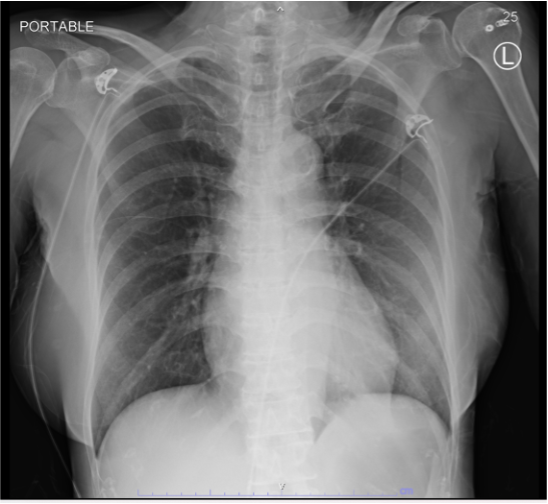

Electrocardiogram (ECG) was performed-showing sinus rhythm 60 bpm with ST-segment elevation in leads II, III, aVF, ST-segment depression in leads I, aVL. ECG show AV dissociation develop to 3rd degree AV block and present bigeminy ST segment elevation PVCs . CXR no pulmonary congestion . High sensitivity troponin-I was requested with highly elevated result as 1,957 ng/L. Echocardiogram showed LVEF 50%, Inferior, inferoseptal and inferolateral wall hypokinesia